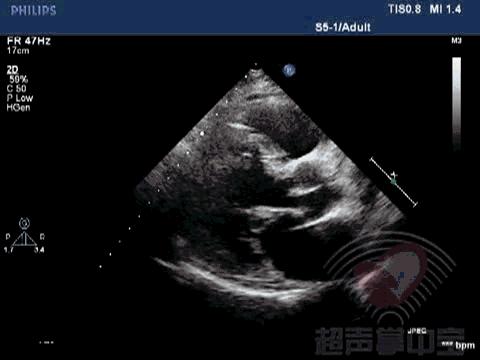

经典病例▏二尖瓣囊肿中竟然全是血液? 动态图3:左室长轴切面视察该囊状物质软,有形变,随二尖瓣运动而摆动

经典病例▏二尖瓣囊肿中竟然全是血液? 动态图4:心尖左室长轴切面视察该囊状物质软,有形变,随二尖瓣运动而摆动